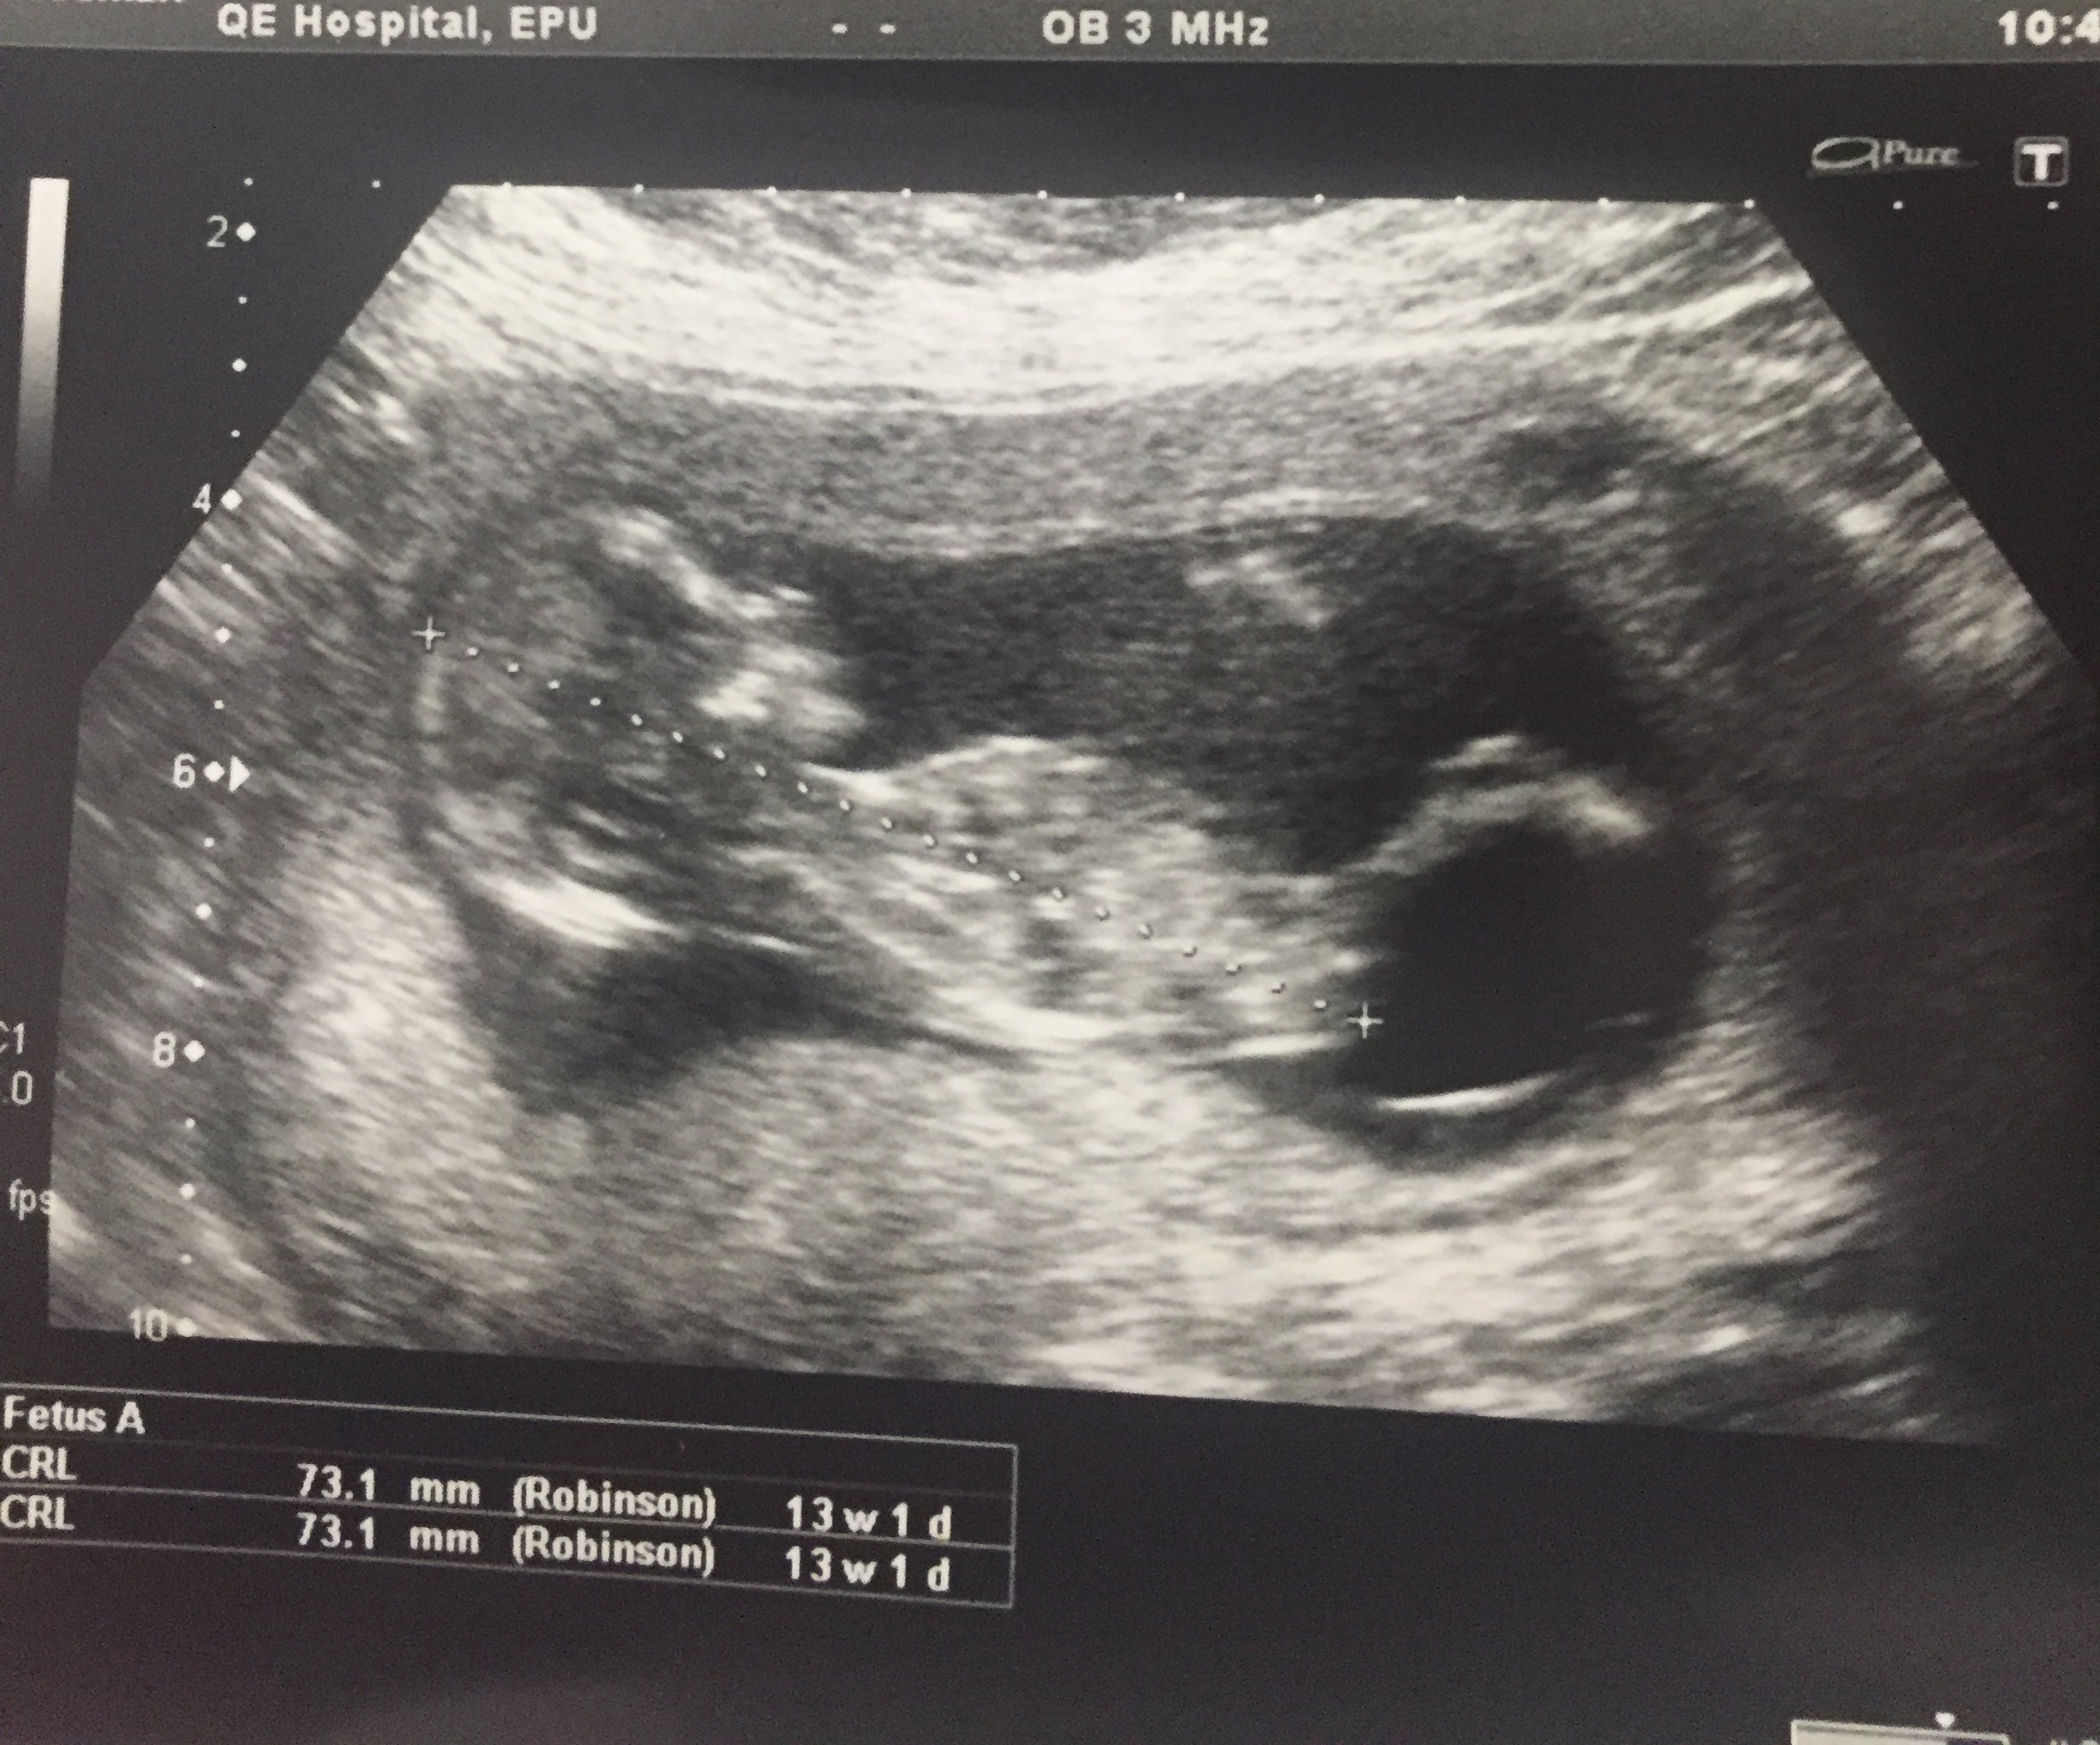

13weeks and 2days please any guesses welcome Attachment 29627

Can anyone clarify if there is a nub in the pic please

No, not a clear nub. The leg stretched out like that would block any nub.